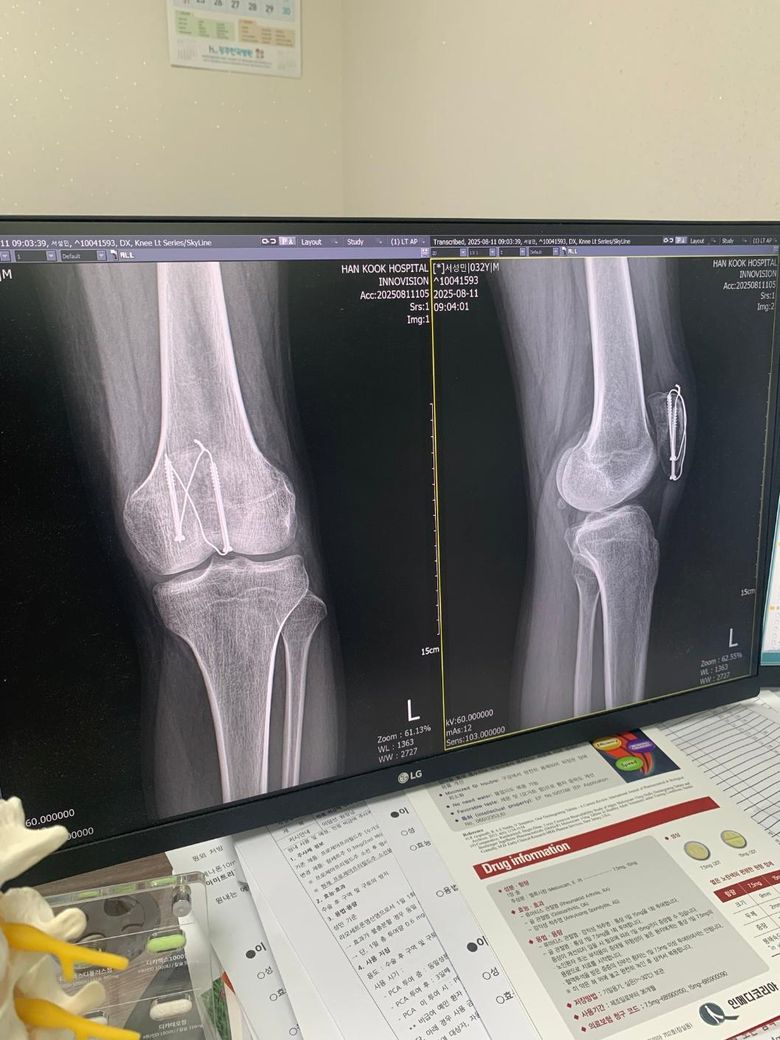

슬개골골절 수술후 8주차 엑스레이입니다 질문좀드릴게여ㅠㅠ

1. 엑스레이상 유합이 잘되고있는건가요?

2. 수술부위를만져보면 한쪽부분이 골절선처럼 움푹파여서 보여지는데 혹시 뼈가 생기다가 만걸까요?

• 2번 째 사진

현재로썬 엑스레이상 유합이 잘되고있는것으로 보여지지만 다방면으로 확인이 필요한 부분이기에 전문의에 소견을 들어보시길 바랍니다.

보통 수술 후 봉합 부위에선 연부조직의 변화로 울퉁불퉁한 느낌이 들 수 있으며, 뼈가 생기다만것은 아니니 걱정하지않으셔도 됩니다.

1. 사진상으로는 수술 이후 금속고정물이 자리를 잡고 골 유합이 이루어지고 있는 것으로 보이는데요, 통증이나 불편감이 심하지 않고 특별히 다른 소견이 없으셨다면 회복이 잘 진행되고 있는 것으로 생각됩니다.

2. 표면의 변화는 뼈의 회복과정에서 일어날 수 있는 표면 변화로 생각됩니다.